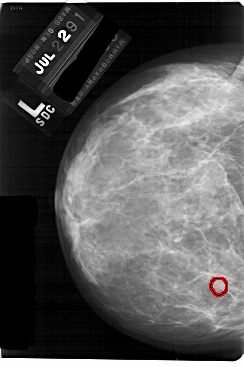

A_1757_1.LEFT_CC

FILE: A_1757_1.LEFT_CC.OVERLAY

TOTAL_ABNORMALITIES 1

ABNORMALITY 1

LESION_TYPE MASS SHAPE ROUND MARGINS OBSCURED

ASSESSMENT 3

SUBTLETY 3

PATHOLOGY BENIGN

TOTAL_OUTLINES 1

BOUNDARY